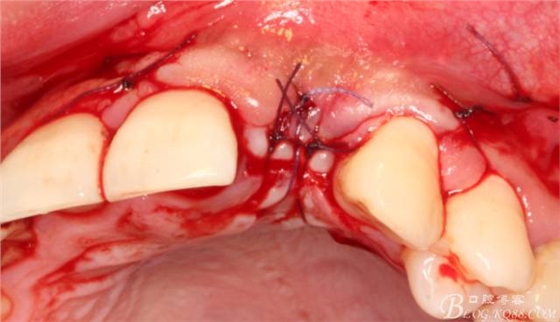

減張縫合。自我感覺一切OK。囑其近期不可劇烈活動,也不要總想著為國足報仇。

10天拆線一切正常,又過了兩周患者復(fù)診,自述期間無異常??趦?nèi)檢查,真的嚇了一跳,唇側(cè)鼓了個包,擠壓有白色分泌物溢出,絕對不是膿液,液體排除后,術(shù)區(qū)觸診空虛,外觀塌陷。這時候考研大夫的時刻到了,是先觀察一段時間再說?還是馬上進(jìn)行處理?我的回答是:馬上處理!如果你沒有及時處理,而是放患者回家觀察,那么接下來會發(fā)生如下情況:1.回家后患者家屬及親友會有很多你可以想象得到的討論;2.患者及家屬會對你產(chǎn)生不信任,勢必會到其他門診或醫(yī)院檢查,他院大夫會不會發(fā)表對你不利的言論;3甚至?xí)蚁嚓P(guān)法律界人士找你討要說法。

于是我果斷告知患者,手術(shù)失敗了,不能拖延,如不及時處理,炎癥繼續(xù)發(fā)展會很快波及鄰牙牙槽骨。患者接受我的建議。切開翻瓣,骨粉及生物膜消失了,骨吸收嚴(yán)重,幸運的是,因為處理及時,鄰牙骨支持依然存在。